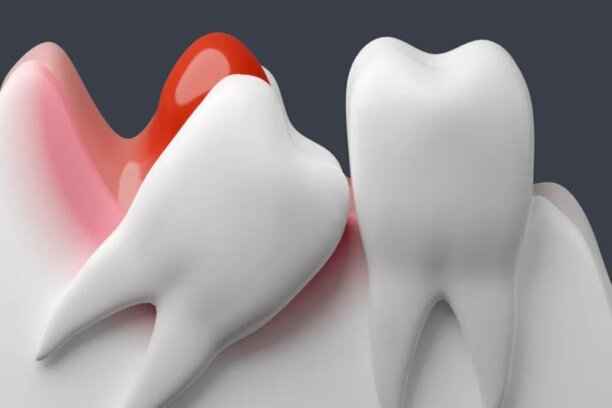

شكل ضرس العقل

يختلف شكل ضرس العقل من شخص لآخر، إلا أنه غالبًا ما يتميز بحجم أكبر وجذور أكثر تعقيدًا مقارنة ببقية الأضراس. قد يكون مكتمل التكوين أو مشوهًا جزئيًا، وقد يظهر بشكل عمودي أو مائل أو حتى أفقي. هذه الاختلافات الشكلية تلعب دورًا مباشرًا في حدة اعراض ضرس العقل. ومن أبرز السمات الشكلية الشائعة:

• تاج ضخم ذو نتوءات غير منتظمة.

• جذور طويلة أو متشابكة يصعب التعامل معها جراحيًا.

• ميلان واضح نحو الضرس المجاور أو باتجاه عظم الفك.

• بزوغ جزئي يترك جزءًا من الضرس مغطى باللثة.

• تموضع عميق داخل العظم دون ظهور مرئي.

كل هذه الأشكال قد تكون شرارة أولى لظهور اعراض ضرس العقل بشكل مزمن.